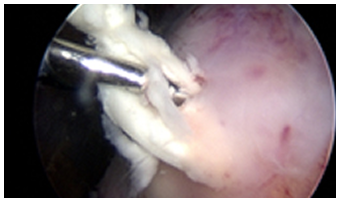

관절내시경

관절내시경은 무릎과 어깨뿐만 아니라 최근에는 팔꿈치, 손목, 발목 등 작은 관절에서도 관절 질환을 진단하고 치료하는 데 매우 유용한 방법입니다.

약 5mm 정도의 작은 피부 절개를 통해 초소형 카메라와 수술 도구가 장착된 내시경을 관절 내부로 삽입하여 병변을 직접 확인한 후, 치료 방법을 결정하여 병변을 제거하거나 복원하는 치료를 시행합니다. 절개가 거의 없어 제한된 부위 내에서 수술이 이루어지므로, 난이도가 높은 경우가 많아 반드시 숙련된 내시경 전문의에게 수술을 받아야 만족스러운 결과를 기대할 수 있습니다.

관절 내시경은 무릎과 어깨뿐만 아니라 팔꿈치, 손목, 발목 등 작은 관절의 질환까지 진단과 치료를 동시에 할 수 있는 매우 유용한 방법입니다.

약 5mm 정도의 피부 절개를 통해 초소형 카메라와 수술 도구가 부착된 내시경을 삽입하여, 관절 내부의 병변을 확인한 후 이를 제거하거나 봉합하는 치료를 진행합니다. 절개가 거의 없어 제한된 부위 내에서 수술을 시행하기 때문에 수술의 난이도가 높은 경우가 많이 있어 반드시 숙련된 내시경 전문의에게 수술을 받아야 만족할 만한 결과를 보장할 수 있습니다.